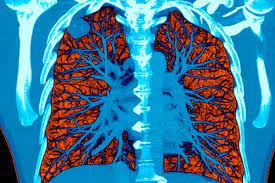

How To Detect Lung Cancer Ct Scan : Serial Chest Ct Scans A At The Time Of The Small Cell Lung Cancer Download Scientific Diagram / This provides a series of images from many different angles.. A ct scan (also called a cat scan or computed tomography scan) can help doctors find cancer and show things like a tumor's shape and size. This lung cancer awareness month learn how future processing is able to detect lung cancer from ct scans with the help of ai. The computer puts them together to make a 3 dimensional (3d) image. How does a ct or cat scan work? It can also show the size, shape, and position of any lung tumors and can help find enlarged lymph nodes that might contain cancer that has spread.

Understanding Your Chest Ct Scan Pet Scan For Lung Cancer Detection from www.docpanel.com As a ct scan detects abnormal tissue, it is useful for planning areas for radiotherapy and biopsies. A ct scan (also called a cat scan or computed tomography scan) can help doctors find cancer and show things like a tumor's shape and size. Ct (or cat) stands for computed (axial) tomography. Lung cancer detection using ct scan. Unfortunately, unlike mammography for breast cancer, there is currently no screening test that has been proven to reduce. What is ct lung cancer screening? A ct scan can help to diagnose lung cancer. This lung cancer awareness month learn how future processing is able to detect lung cancer from ct scans with the help of ai.

How to detect lung cancer: The computer puts them together to make a 3 dimensional (3d) image. They can also show the size, shape, and position of any lung tumors and can pet scan: Early detection of lung cancer (detection during the earlier stages). All these works involved mainly three steps to detect the. Also, because of the inability to detect calcium with mri, enlarged and calcified benign nodes may be mistaken for pathologic nodes. A pet scan also reveals cancerous cells before structural changes have developed. Pet and nuclear medicine scans. What to expect when undergoing this test. The primary goal of lung cancer screening ct is to detect abnormalities that may represent lung cancer and may require further scan range • from top of lungs through the bottom of lungs. Abstract—lung nodules are potential manifestations of lung cancer, and their early detection facilitates early treatment and improves patient's for this reason, cad systems for lung cancer have been proposed in several studies. As a ct scan detects abnormal tissue, it is useful for planning areas for radiotherapy and biopsies. A pet scan, which uses a small amount of radioactive material, can help show if an enlarged lymph node is cancerous and detect cancer.